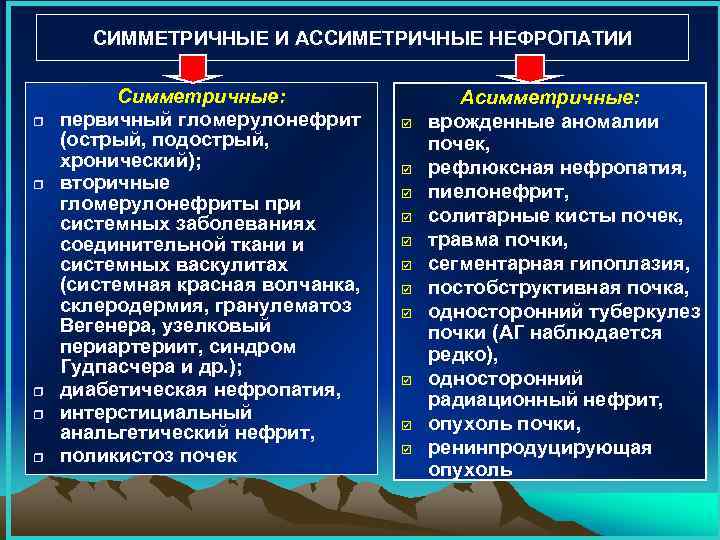

СИММЕТРИЧНЫЕ И АССИМЕТРИЧНЫЕ НЕФРОПАТИИ r r r Симметричные: первичный гломерулонефрит (острый, подострый, хронический); вторичные гломерулонефриты при системных заболеваниях соединительной ткани и системных васкулитах (системная красная волчанка, склеродермия, гранулематоз Вегенера, узелковый периартериит, синдром Гудпасчера и др. ); диабетическая нефропатия, интерстициальный анальгетический нефрит, поликистоз почек þ þ þ Асимметричные: врожденные аномалии почек, рефлюксная нефропатия, пиелонефрит, солитарные кисты почек, травма почки, сегментарная гипоплазия, постобструктивная почка, односторонний туберкулез почки (АГ наблюдается редко), односторонний радиационный нефрит, опухоль почки, ренинпродуцирующая опухоль

СИММЕТРИЧНЫЕ И АССИМЕТРИЧНЫЕ НЕФРОПАТИИ r r r Симметричные: первичный гломерулонефрит (острый, подострый, хронический); вторичные гломерулонефриты при системных заболеваниях соединительной ткани и системных васкулитах (системная красная волчанка, склеродермия, гранулематоз Вегенера, узелковый периартериит, синдром Гудпасчера и др. ); диабетическая нефропатия, интерстициальный анальгетический нефрит, поликистоз почек þ þ þ Асимметричные: врожденные аномалии почек, рефлюксная нефропатия, пиелонефрит, солитарные кисты почек, травма почки, сегментарная гипоплазия, постобструктивная почка, односторонний туберкулез почки (АГ наблюдается редко), односторонний радиационный нефрит, опухоль почки, ренинпродуцирующая опухоль